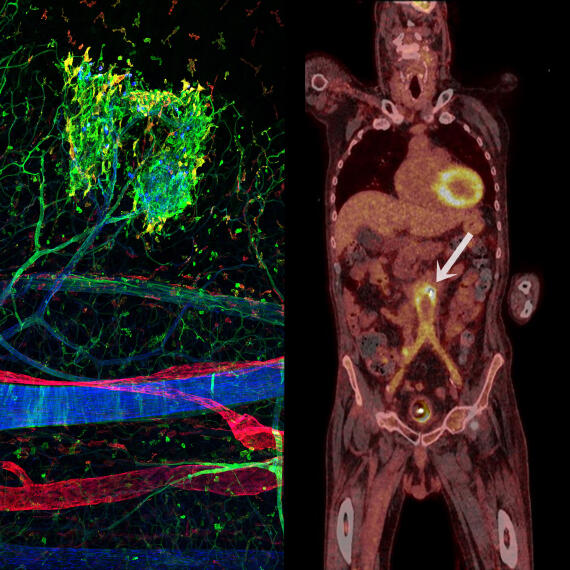

Darstellung von Entzündungen mittels Mikroskopie (links) und Ganzkörperbildgebung (PET-CT, rechts)

© Uni MS – AG Kiefer/AG Schäfers

Sonderforschungsbereich „inSight – Darstellung organspezifischer Entzündung durch multiskalige Bildgebung“ (SFB 1450)

In diesem Verbundforschungsprojekt befassen wir uns mit der Frage, wie der Körper Entzündungen in unterschiedlichen Organen reguliert, und entwickeln hierzu eine spezifische Bildgebungsmethodik, mit der sich Informationen von der einzelnen Zelle bis zum gesamten Organismus zusammenbringen lassen.